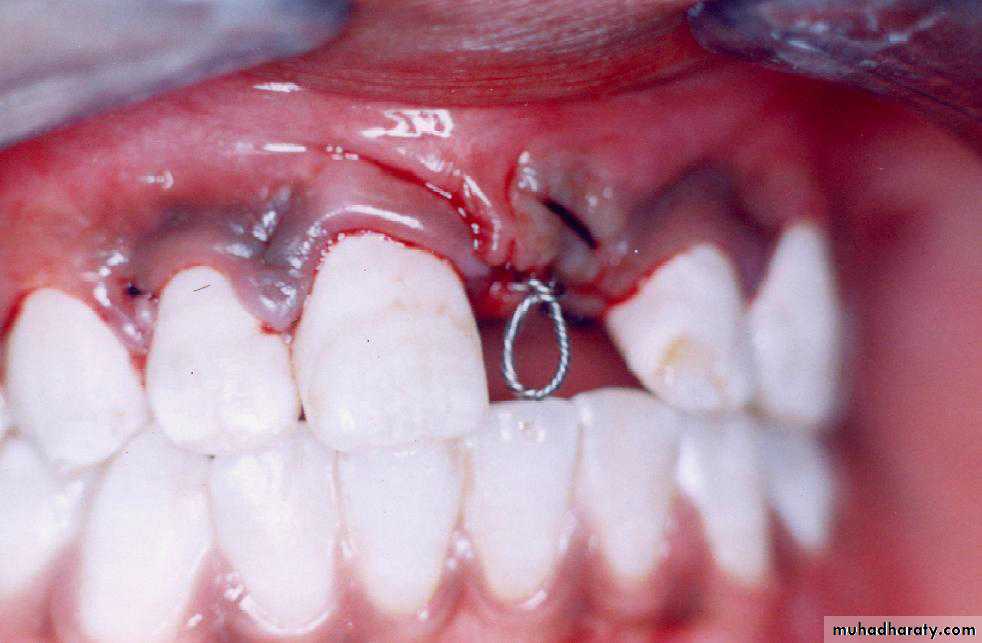

Surgical exposure with orthodontic traction: the path of eruption is obstructed

Surgical exposure with orthodontic treatment (palatal approach )